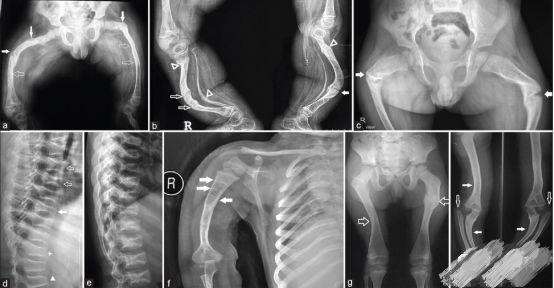

OI标志性特征是骨质脆弱反复骨折, 典型骨骼X线表现(见图二);成骨不全症的临床表现不仅限于骨骼,还常常累及其他结缔组织如眼、耳、皮肤、牙齿等(见图三)。根据临床表型, 澳洲悉尼大学的Sillence教授将OI 分成至Ⅰ-Ⅳ型[7]: Ⅰ型病情最轻, 最常见; Ⅱ最重, 通常围产期致死; Ⅲ型是存活者中最严重的, 常常身材矮小, 呈进行性骨骼畸形; Ⅳ型严重度介于Ⅰ型与Ⅲ型之间。近期发现的Ⅴ型OI 具有肥厚性骨痂、桡骨头脱位、前臂骨间膜钙化、桡骨干骺端下密集骺线等独特临床表现(见图四)。

图二:成骨不全症典型的X线表现

a.股骨干侧位片显示双侧非对称的股骨前弓弯曲愈合中的骨折(实心箭头)和已经愈合的骨折(空心箭头)

b. 胫骨侧位片显示双侧胫骨向前弯曲以及骨折愈合的不同阶段:早期愈合(实心箭头),进行性愈合中(空心箭头),已经愈合(三角);双侧胫骨呈现铅笔样畸形,尤其是腓骨及蜂巢状髓腔,特别是胫骨远端。

c. 骨盆平片显示严重的股骨近端髋内翻畸形以及基本完全愈合的转子下骨折;骨折愈合一般从内侧(压应力侧)开始,而骨折不愈合通常发生外侧表面(张应力侧);

d. 胸腰段脊柱侧位片显示椎体及附件广泛骨质疏松,椎体呈双凹征(空心箭头),扁平椎(实心箭头)以及各种程度的椎体前方楔形变,总的来说成骨不全患者脊柱骨骼改变与生长激素替代治疗的骨骼改变表现非常类似,骨硬化与骨吸收相互交错;

e. 肱骨的前后位片可以看到多条横形的硬化带,代表的是双磷酸盐治疗周期;同时还可以看到向外拉长、变薄变细的锁骨和肋骨以及增宽的肋间隙;

g.皮肤松弛症的X线片表现有时与成骨不全的比较类似,股骨干前后位片显示已经愈合的股骨干骨折;

h.上肢的前后位片显示双侧的尺骨向外侧弯曲成角,肱骨远端向内侧成角(实心箭头),同时伴有桡骨小头脱位(空心箭头)。